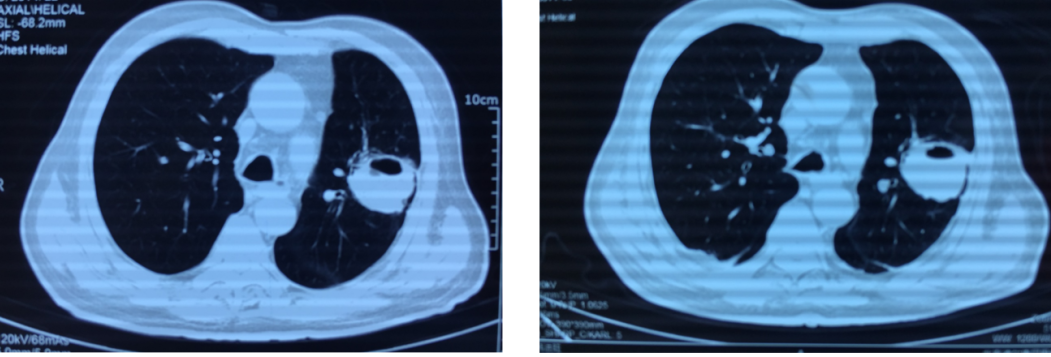

腰椎MRI检查提示「腰1-3水平椎管内及腰骶部,双侧腰大肌、竖脊肌内多发异常强化」,胸部CT提示左上肺类圆形厚壁空洞影,偏心性空洞。

复查胸部CT(图4)左肺空洞较前无明显变化。

病人第一次做胸部CT(左图,2019-3-4),明显看到左上肺类圆形厚壁空洞影,偏心性空洞。痰培养肺炎链球菌,但美罗培南治疗效果不佳。

治疗后复查

抗感染治疗2周后复查胸部CT(右图,2019-3-20),较前吸收不明显,似乎还有一些增长的情况,提示给我们什么呢?查不到病原学导致不好治疗,为什么在明确病原学的情况下,治疗后影像学几乎没有变化呢?其实这个时候告诉大家,这样的病例应该积极明确穿刺,去寻找其他的病因。

入院后安排穿刺后提示肺鳞癌,伴坏死。免疫组化 CK7(-),Ki67(约 50% 阳性)。经过化疗和局部放疗后,病人得到改善。